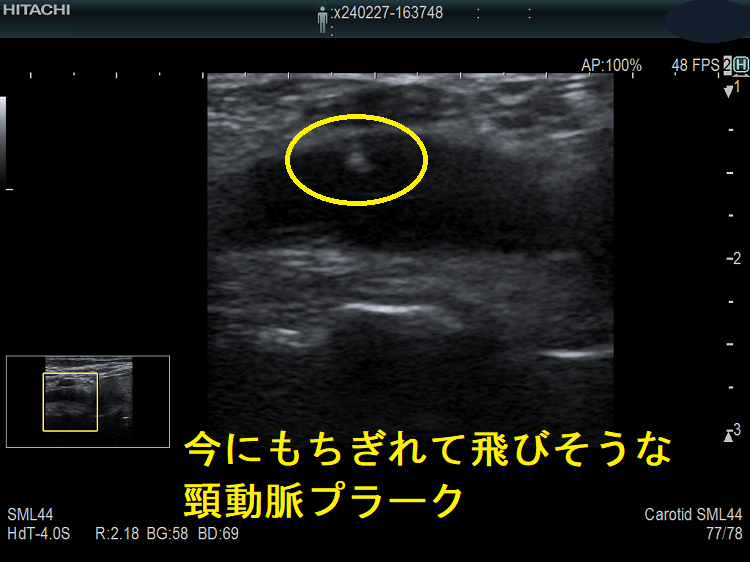

動脈硬化が進んだ血管にはプラーク(コレステロールエステルを大量に含んだ脂質の塊)(矢印)ができて、血管内が狭くなります。血管エコーでプラークを探す。動脈硬化した血管は硬くもろいため、大動脈では血圧に負けて大動脈瘤になることがあります(急性大動脈解離・大動脈瘤)。

甲状腺機能低下症/潜在性甲状腺機能低下症/橋本病、糖尿病などでは動脈硬化が進み(甲状腺と動脈硬化)、頚動脈プラークを形成。頚動脈プラークに血栓ができると、脳へ流れ込んで脳梗塞を引き起こします。最悪、頚動脈そのものが閉塞する事もあります。

(↓)デジタルハイビジョン超音波装置で見たプラーク。